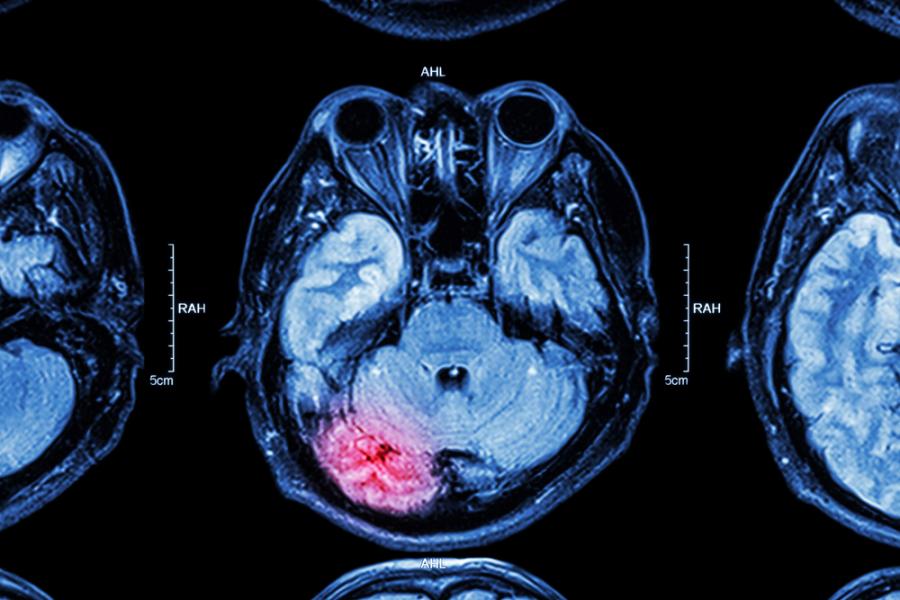

Неврохирургът Джослин Блок познава отлично неспособността на мозъка да се възстановява сам благодарение на срещите си с всевъзможни случаи - от удари до травми след автомобилни катастрофи.

Сега обаче тя предполага, че с колегите ѝ може да са открили ключа към мозъчното оздравяване - двойно позитивните кортикални клетки. Подобно на стволовите клетки, те са изключително адаптивни и извлечени от мозъка, култивирани и после инжектирани обратно в увредена област на същия мозък, могат да му помогнат да оздравее и да се възстанови.